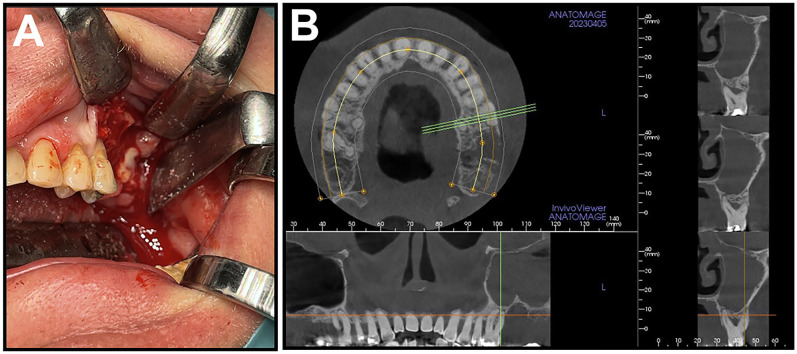

药物相关性颌骨骨坏死(MRONJ)是抗吸收治疗的一种日益常见的后果,它通常导致坏死暴露的骨表面的发展,并伴有影响颌骨的炎症过程。虽然MRONJ的发展通常与口腔微生物群定植成员引起的炎症反应或感染有关,但MRONJ的确切发病机制尚不完全清楚。在本文中,我们旨在提供额外的微生物培养支持的证据,支持“感染假说”,即放线菌及其相关生物可能在MRONJ的发展和导致的骨坏死中发挥重要的致病作用。在我们的病例系列中,所有患者都有相似的基础疾病和遗忘数据,并接受了抗吸收药物(双膦酸盐或RANK配体(RANKL)抑制剂),以预防继发于前列腺癌的骨转移的发生或进展。然而,在抗吸收药物治疗的几年中,在上述患者中发现了不同阶段的MRONJ。在所有三个病例中,坏死骨样本的定量微生物培养产生了一个复杂的微生物群,以放线菌和沙利亚菌为主,菌落数量高。此外,我们的随访病例系列记录了这些患者联合手术干预和长期抗生素治疗的治疗情况,所有病例都有良好的临床反应。如果“感染假说”是有效的,它可能对与该疾病相关的预防和治疗策略产生重大影响。

Medication-related osteonecrosis of the jaw (MRONJ) is an increasingly common consequence of antiresorptive treatment, which often leads to the development of necrotic exposed bone surfaces with inflammatory processes affecting the jawbone. Although the development of MRONJ is often associated with the inflammatory response or infections caused by the colonizing members of the oral microbiota, the exact pathogenesis of MRONJ is still not fully understood. In the present paper, we aimed to provide additional, microbiological culture-supported evidence, supporting the "infection hypothesis" that Actinomyces spp. and related organisms may play an important pathogenic role in the development of MRONJ and the resulting bone necrosis. In our case series, all patients presented with similar underlying conditions and anamnestic data, and have received antiresorptive medications (bisphosphonates or a RANK ligand (RANKL) inhibitor) to prevent the occurrence or progression of bone metastases, secondary to prostate cancer. Nevertheless, a few years into antiresorptive drug therapy, varying stages of MRONJ was identified in the mentioned patients. In all three cases, quantitative microbiological culture of the necrotic bone samples yielded a complex microbiota, dominated by Actinomyces and Schaalia spp. with high colony counts. Additionally, our followed-up case series document the treatment of these patients with a combination of surgical intervention and long-term antibiotic therapy, where favourable clinical responses were seen is all cases. If the "infection hypothesis" is valid, it may have significant consequences in the preventative and therapeutic strategies associated with this disease.